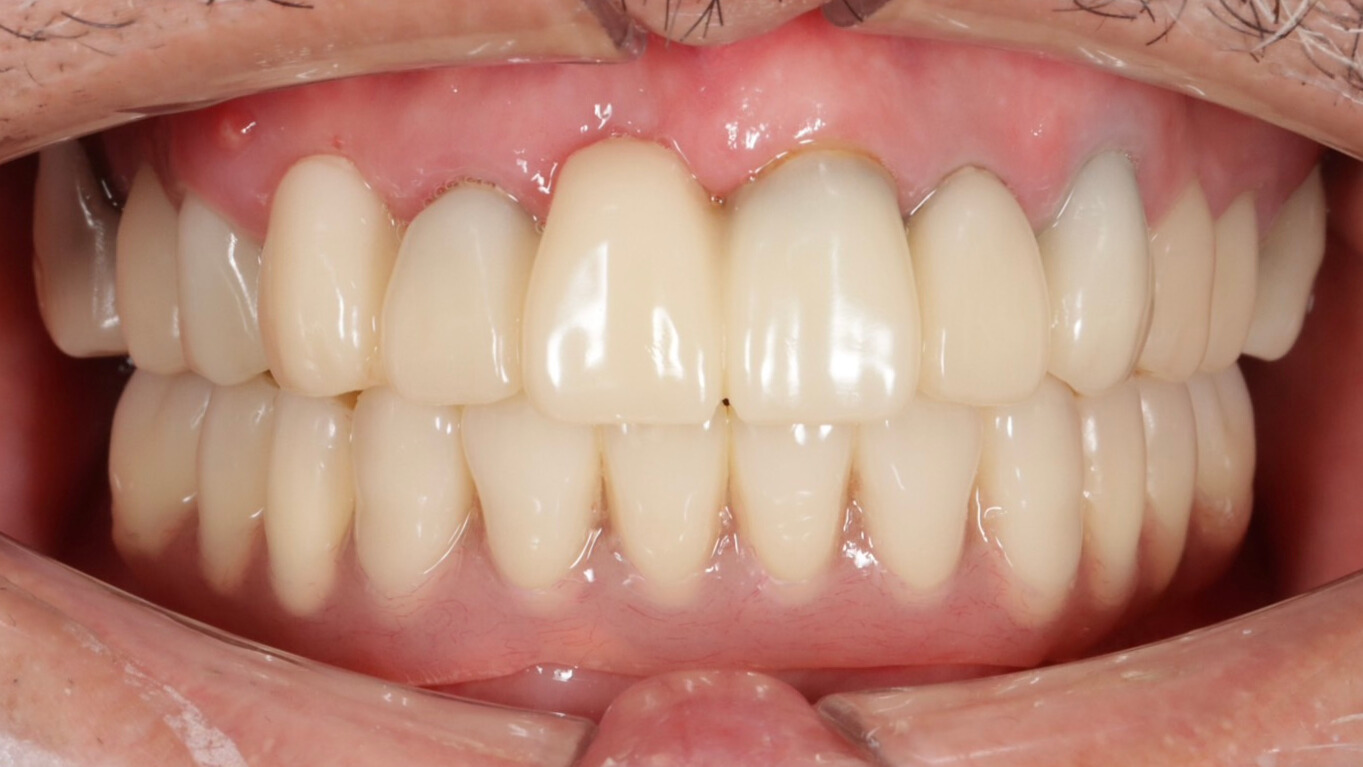

治療後

| 治療内容 | 入れ歯が嫌で、固定式の歯を希望された患者様です。 オールオン4治療を行い、下顎に4本のインプラントを埋入し、オペ当日に即日仮歯を入れました。 |